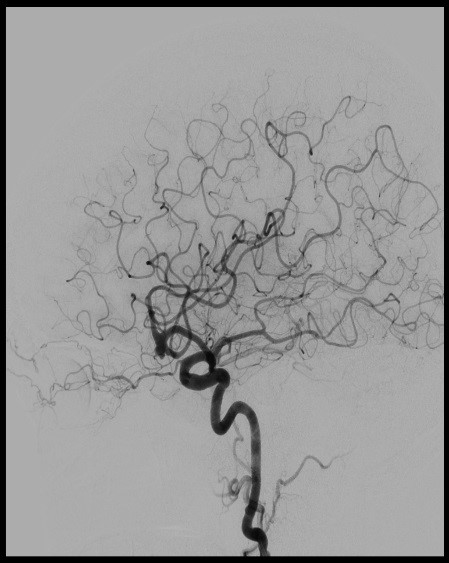

The biplane utilizes two rotating cameras, one on each side of the patient, to produce simultaneous and highly detailed images of blood vessels, soft tissue, and blood flow in real-time.

3-D biplane imaging helps clinicians path blood flow through vessels, locate blockages that cause ischemic strokes, and identify aneurysms and arteriovenous malformations (a tangle of arteries and veins) that cause hemorrhagic strokes.

Biplane imaging is the gold standard in interventional medical imaging technology and enables:

- Faster, more accurate diagnostic and treatment decisions for stroke patients

- Easy-to-read, real-time views of brain perfusion in greater detail

- Dynamic analysis to visualize and analyze image data, show contrast changes over time, and monitor parameters related to blood flow

Combining diagnosis and treatment into one procedure saves precious time and can make all the difference in recovery for patients with acute stroke or severe neurovascular complications.